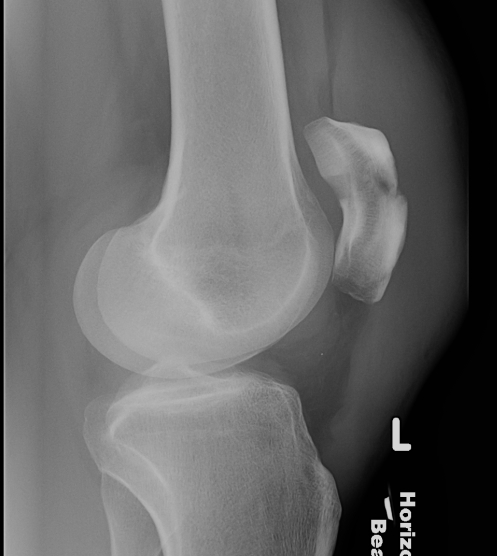

2. Transverse

Displaced transverse fractures